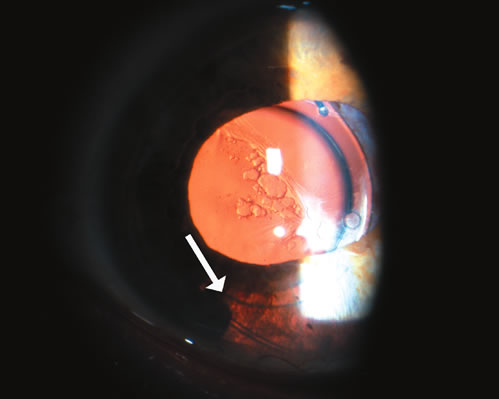

One of the more common reasons for focal iris atrophy in recent years is found in eyes that have undergone extracapsular cataract extraction with placement of an intraocular lens implant.45,47 This is an erosion phenomenon that occurs with anterior chamber lens and sulcus fixated lens (Fig. 7).48,49 Iris atrophy is also seen commonly around surgical or laser iridectomies.

Fig. 7. Iris atrophy with transillumination defects (arrow) after extracapsular cataract surgery with a sulcus fixated intraocular lens. (© University of Illinois at Chicago.)